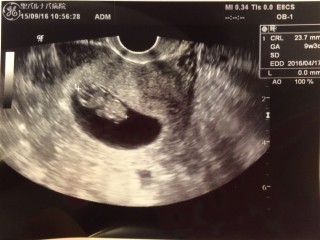

先生が「今見えた?ダンスしてるよ」って言われて 先生がお腹を軽くさすると ピョコピョコって動きました(^^) 思わずかわいい!って言っちゃいました。 23.6mm 全快は少し小さめで心配でしたが、一日分大きくなっていました